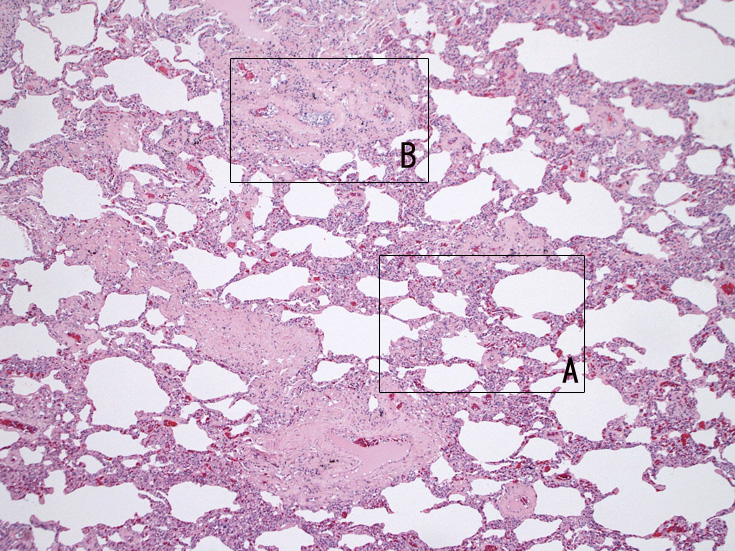

肺A;肺胞壁が厚くなり毛細血管内に腫瘍細胞が多数出現している(A).

肺B;小気管支動脈, 肺動脈内を腫瘍細胞が閉塞する. 動脈内膜に浸潤性増殖している(B)。